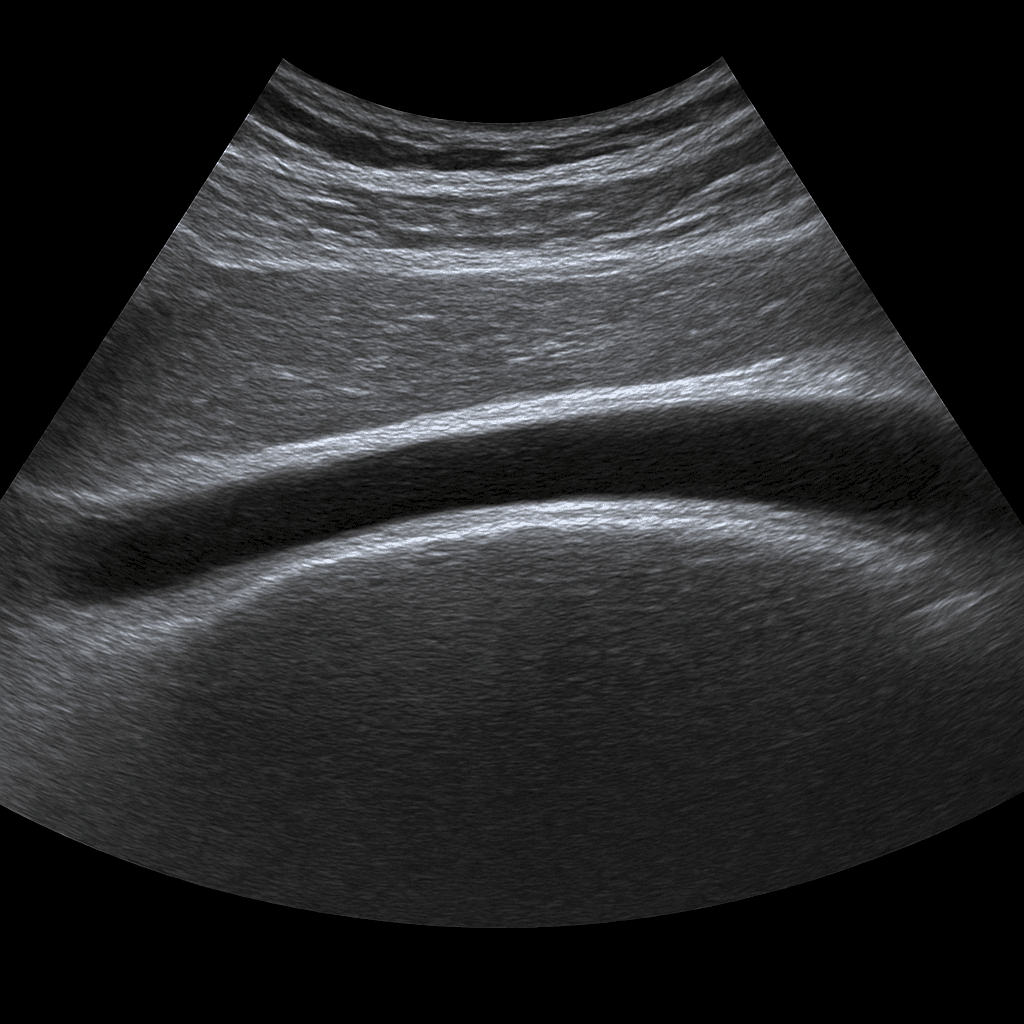

Ultraljud Hälsena – undersökning av hälsenan och dess fästen

Ett ultraljud av hälsena används för att bedöma hälsenans struktur, blodcirkulation och omgivande vävnader. Undersökningen utförs av specialistläkare inom radiologi och ger detaljerade bilder i realtid av senans tillstånd. Den kan påvisa eventuell inflammation, bristningar, kalkinlagringar eller ärrbildningar som orsakar smärta eller nedsatt funktion i foten.

Undersökningen utförs medan du ligger eller sitter med foten lätt böjd. En gel appliceras på huden för att ge optimal kontakt mellan sonden och huden. Läkaren för ultraljudsproben längs hälsenan och bedömer strukturen i både längd- och tvärsnitt. Vid behov kan dynamiska rörelser göras för att se hur senan reagerar vid belastning.